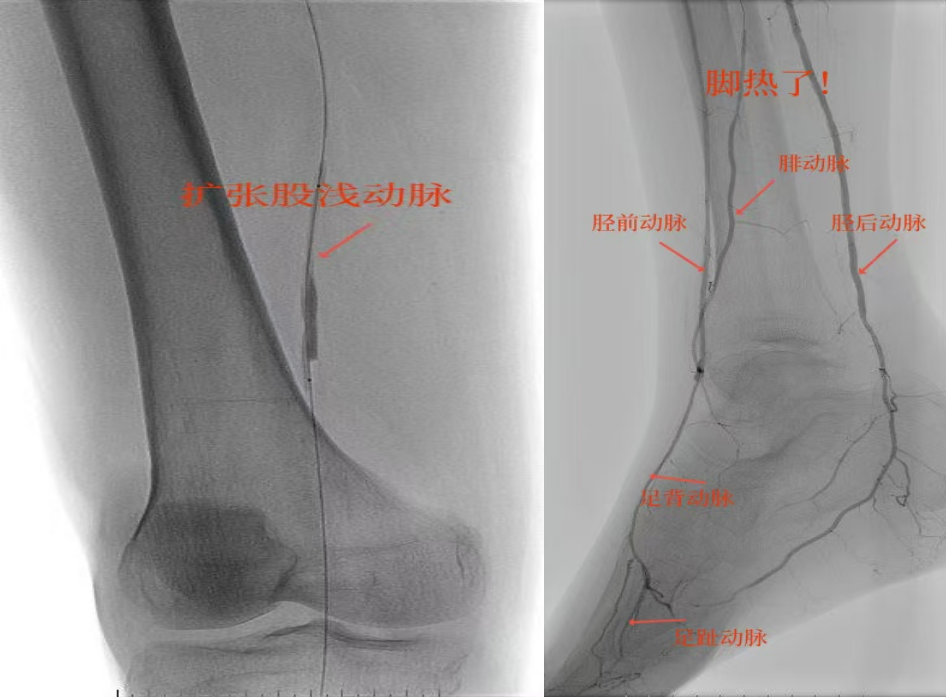

67岁女性患者,多年糖尿病、冠心病史,因右足溃烂伴凉麻疼痛长达2年就诊,此前曾接受外院介入术后血管再度闭塞。此次检查发现其股浅动脉、腘动脉至膝下血管全程闭塞,且伴有严重钙化。团队迎难而上,创新性经足背动脉逆向穿刺,耗时3小时成功贯通胫前动脉。术后当夜患者足部即感回暖,溃烂足趾疼痛显著缓解。术后结合中药外治(换药、熏洗、去腐生肌膏外敷)加速创面愈合。该患者已于出院,院外换药治疗。

影像检查:股浅动脉、腘动脉至膝下血管全程闭塞伴严重钙化。

78岁男性患者,糖尿病合并高血压、脑梗塞,右足持续疼痛伴冰凉发绀3个月。入院CTA显示其右侧股浅动脉全程闭塞,膝下三支动脉均闭塞。医疗团队在局部麻醉下,再次巧妙应用“逆向开通技术”,经胫后动脉——足底弓逆向开通足背动脉及胫前动脉。术后患者右足皮温即刻回升,疼痛消失。术后结合中药外治(换药、熏洗、去腐生肌膏外敷)加速创面愈合,患者已顺利出院。

影像检查:CTA显示右侧股浅动脉全程闭塞,膝下三支动脉(胫前、胫后、腓动脉)完全闭塞。